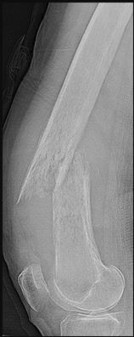

Question 9

A 72-year-old female on prolonged bisphosphonate therapy presents with thigh pain.

Radiographs show a fracture of the femoral shaft. Which of the following radiographic features is most characteristic of an atypical femur fracture associated with bisphosphonate use?

Explanation

Atypical femur fractures (AFFs) associated with prolonged bisphosphonate therapy have specific major criteria defined by the ASBMR. These include a location anywhere from just distal to the lesser trochanter to just proximal to the supracondylar flare, transverse or short oblique orientation, non-comminuted (or minimally comminuted), and originating at the lateral cortex with localized periosteal or endosteal thickening ('beaking').